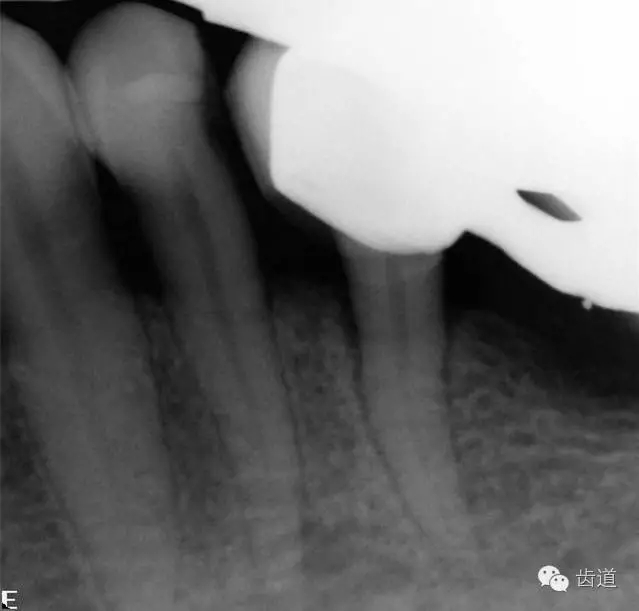

2、45,46術(shù)前片顯示根管上段充填物,根管影像不清晰,少許根尖暗影

1、45,46牙體缺損,慢性根尖周炎(不良根管治療術(shù)后)

1、45,46根管再治療,試保留患牙,擇期冠修復(fù)。

45,46去除原充填物和齲壞,揭全髓室頂,46探及近頰近舌遠(yuǎn)中三根管,45單根管,超聲輔助清理髓腔及根管,去除根管內(nèi)充填物,根管下段細(xì)小堵塞欠通暢,8號(hào)/10號(hào)C銼疏通根管,pathfile+protaper鎳鈦根管預(yù)備,熱牙膠根管充填。